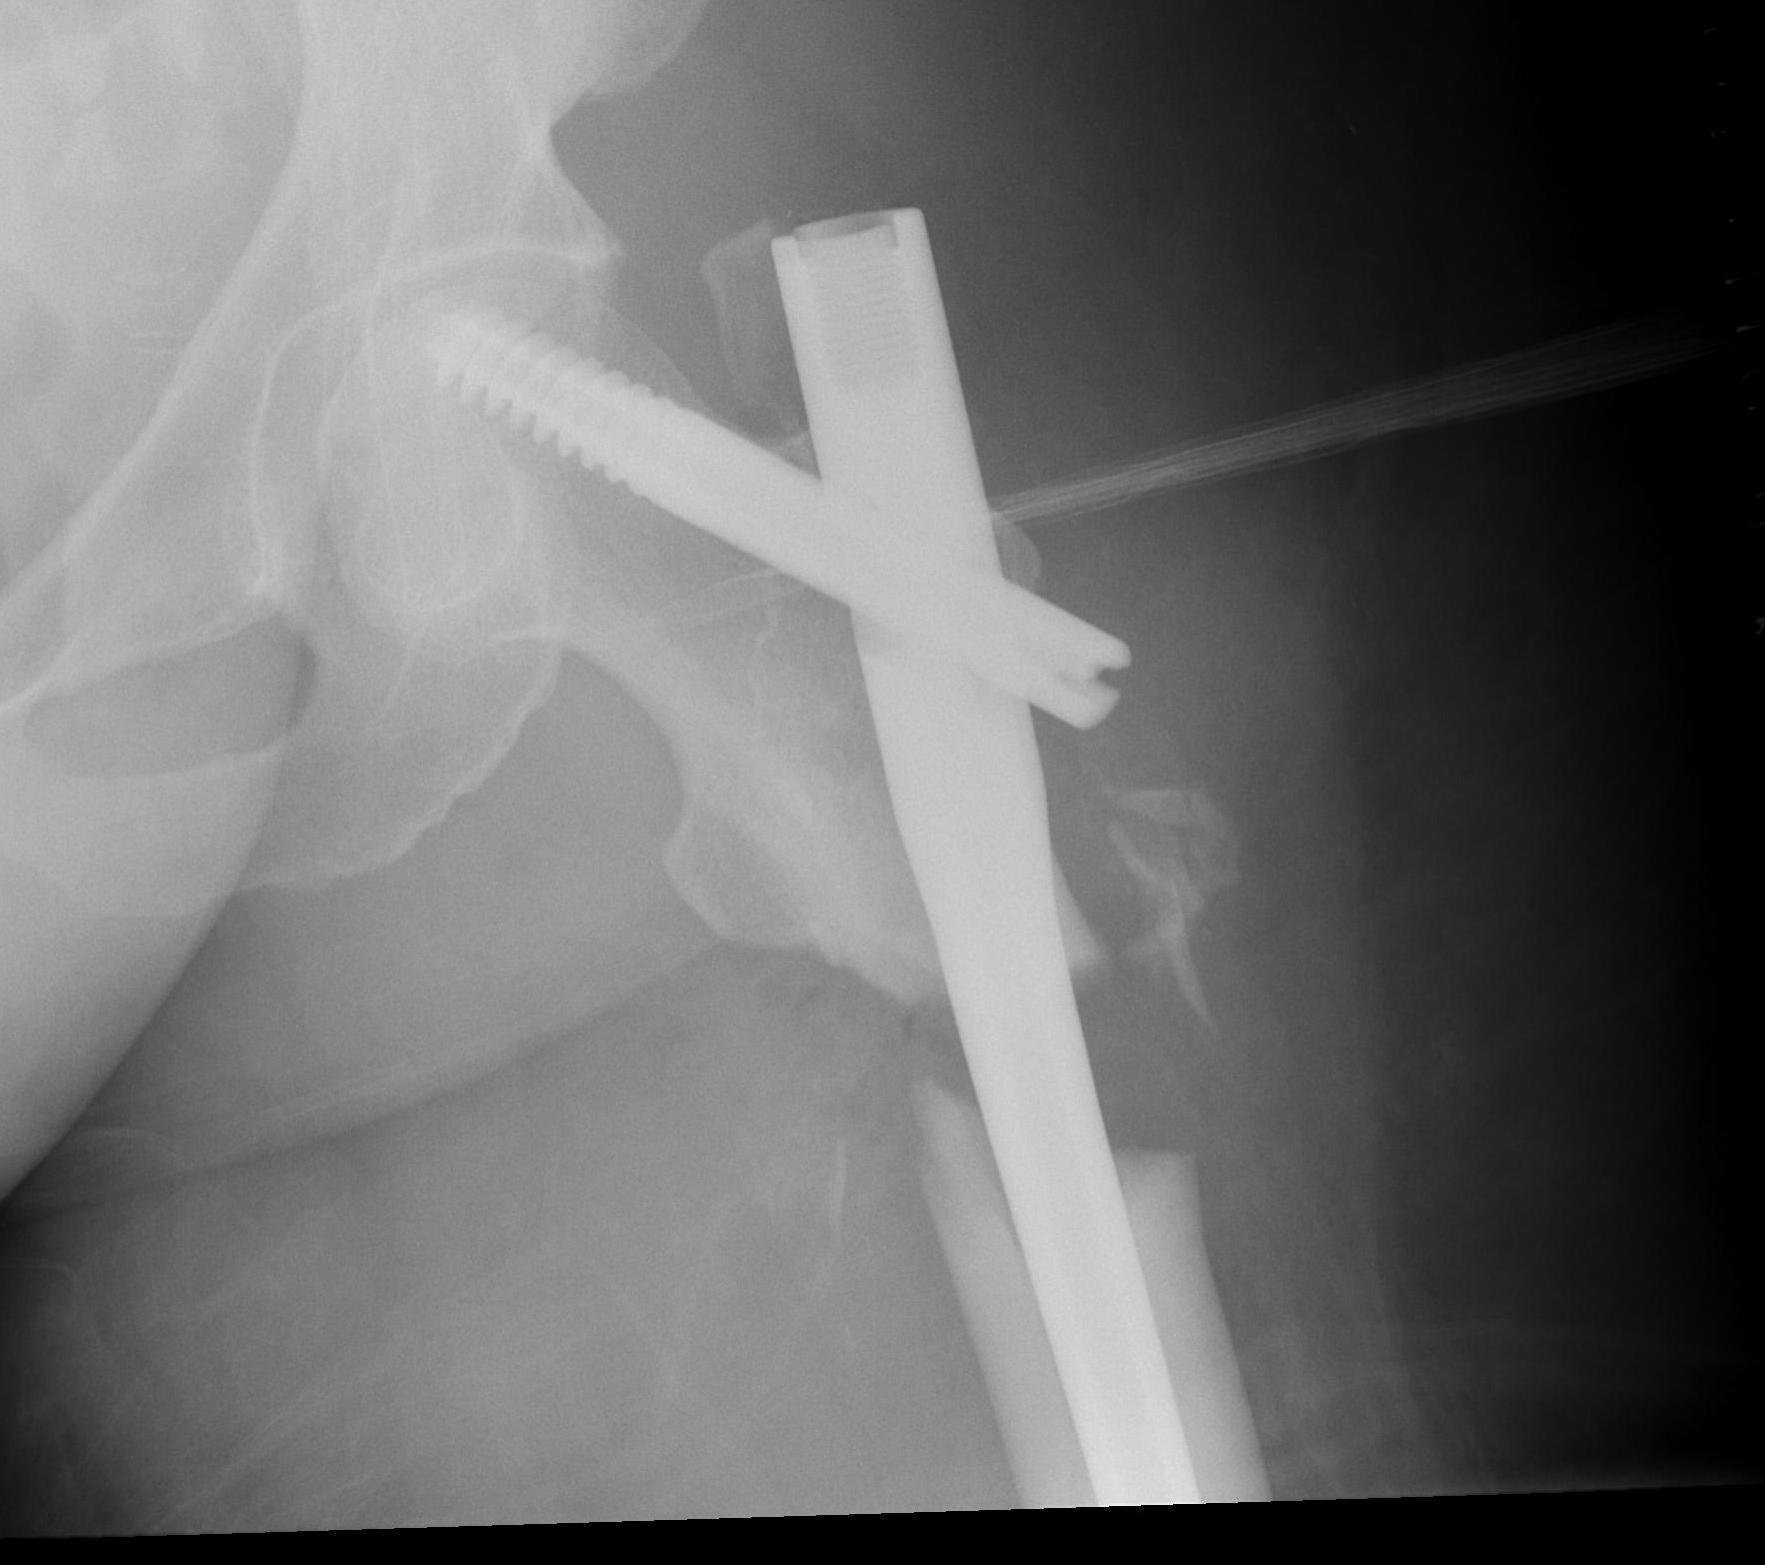

Entry point

Greater trochanteric

- simple

- need proximal fragment reduced

Piriformis

- may aid reduction, as a trochanteric nail will push proximal fragment into valgus

- more difficult to obtain

Reduction techniques

Percutaneous

- ball tipped spikes to reduce deformity

- steinman pins to proximal and distal fragment to reduce deformity

- blocking screws laterally and posteriorly in proximal fragment

Open

1. Short transverse fracture

- clamps on proximal and distal fragments and hold reduced

- consider unicortical small plate to hold reduction

- consider blocking screws